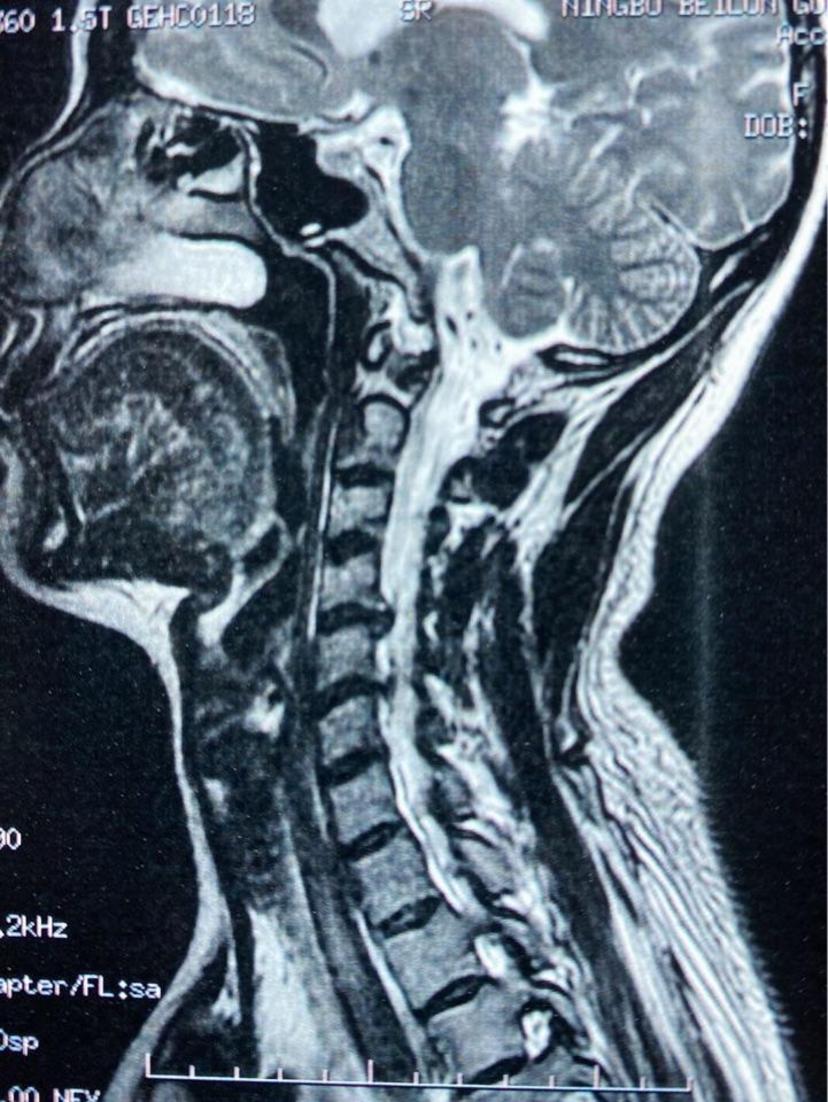

患者颈痛10年,诊断颈椎病,曾多次给予针灸、小针刀、口服药物等治疗,效果不明显,手麻及行走不稳逐渐加重,经CT及磁共振检查后,诊断两节段椎间盘突出合并严重后纵韧带骨化,经前路ACCF微创手术,完全去除了压迫神经脊髓的物体,术后当晚明显感到四肢力量增大,麻木感好转,第二天自行下地行走,第三天康复出院!两节段颈椎间盘突出

术后第三天康复出院